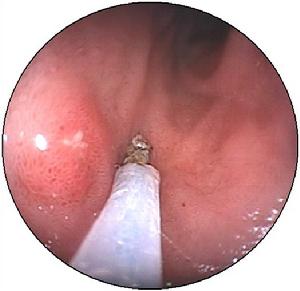

胃息肉(1)高頻電凝切除法:是目前套用最廣泛的方法,其原理是利用高頻電流產生的熱效應使組織凝固、壞死而達到切除息肉的目的。一般電流頻率在300kHz以上,輸出功率為30~80W。術前應儘量抽吸胃內液體,小於0.5cm的無蒂息肉應首選前端球形的電凝器或電熱活檢鉗電凝灼除。使用電熱活檢鉗時,應先將其頭部咬持輕輕提拉後灼除,對於有蒂及大於0.5cm的無蒂息肉應儘量選擇圈套器切除,但也可用球形電凝器或電熱活檢鉗分次灼除。對有蒂息肉應將圈套器套於蒂上並儘量保留殘蒂1cm左右後通電,以避免組織灼傷過深而致穿孔。對於無蒂息肉灼除時應先以高滲鹽水或1∶10000腎上腺素溶液注入息肉基底部1~2點,每點1.0ml,以免圈套切除時損傷肌層及漿膜層,然後用雙活檢管道內鏡先以抓持鉗提拉息肉頭部,使其基底形成假蒂後再行圈套切除。對過大息肉可分期處理,即先將息肉頭部以圈套器進行部分斜行切除,間隔2周后斜行切除對側部分,如未能完全切除可再重複,直到全部摘除;亦可採用吸引與電凝結合進行治療,即在內鏡前安置吸引套,將電凝用圈套器經活檢孔置於吸引套內槽中,將內鏡送至胃腔內,以吸引套頭端與息肉緊密接觸後,負壓吸引息肉至全部吸入吸引套內,收緊圈套器,退出息肉進行電凝。對於較大有蒂或亞蒂息肉也可採用金屬夾結紮後圈套電凝治療,方法為經內鏡活檢孔置入可鏇式夾閉裝置器,於息肉蒂莖部進行多枚交叉金屬鉗夾,阻斷病灶血供,待息肉頭端呈紫色時,進行圈套電凝切除。採用圈套電凝術時需注意通電前要緩慢收緊圈套襻,並輕輕提拉以避免機械切割所致出血及組織過深灼傷,圈套襻收緊後要先電凝後電切,反覆交替,每次通電時間數秒鐘,也可用混合電流間歇通電治療。